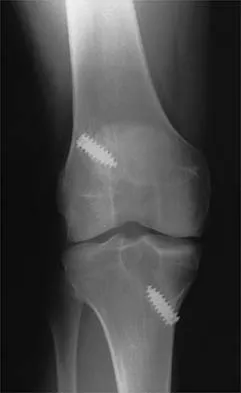

A 24-year-old runner who underwent an allograft reconstruction of the anterior cruciate ligament (ACL) 3 years ago now reports anterior knee pain. Examination reveals no swelling or effusion, and the patient has full motion. A Lachman test and a pivot-shift test are negative. Palpation reveals tenderness on the patellar tendon and at the inferior pole of the patella. AP and lateral radiographs are shown in Figures 41a and 41b. Management should consist of

Explanation